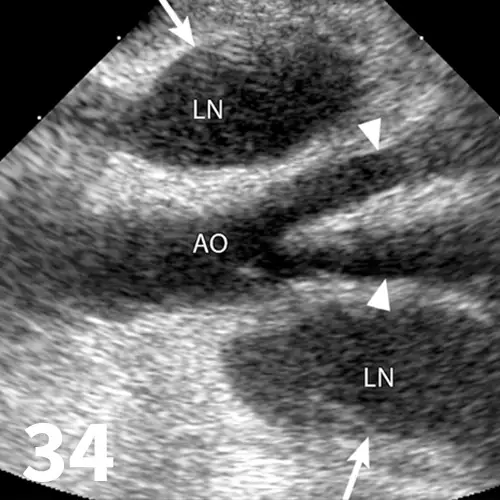

Survey radiography can be used to evaluate the size, shape, and opacity of the prostate gland (Figures 31 and 32). Ultrasonography has the advantage of providing tissue-architecture information. Prostatic abscesses, internal cysts, and paraprostatic cysts are readily visualized on ultrasonography. Ultrasonography can also aid in diagnosing benign hyperplasia (homogenous echotexture with intact capsule) and prostatic neoplasia (heterogenous with course echotexture and irregular margins) (Figure 33) and with identifying any potential source of excess androgen production (eg, adrenal glands, retained testes) in cases of suspected squamous metaplasia of the prostate gland. Mineralization of the prostate in a neutered dog is suggestive of neoplasia and can be detected by both survey radiography and ultrasonography. Sublumbar lymph nodes can also be evaluated by ultrasonography, whereas radiography is best for evaluating the adjacent lumbar spine (Figures 34 and 35).